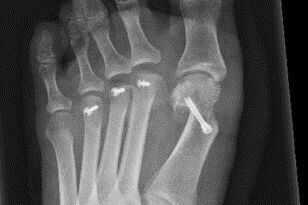

Therapie: distale Umstellung am MT1, Osteotomie an MT 2-4

Die operative Korrektur, bei der Umstellungsosteotomien an den Mittelfußknochen 1-4 links durchgeführt wurden, erfolgte im Mai 2018.

Bei anhaltenden Beschwerden wurde im Mai 2019 eine Röntgenaufnahme durchgeführt, die einen Schraubenüberstand von 1mm am Köpfchen des MT3 ergab. Dieser Befund wurde durch eine CT Untersuchung, bei der zusätzlich eine Arthrose im Grundgelenk der Großzehe und der zweiten Zehe gefunden wurde,  bestätigt.

Röntgenuntersuchungen